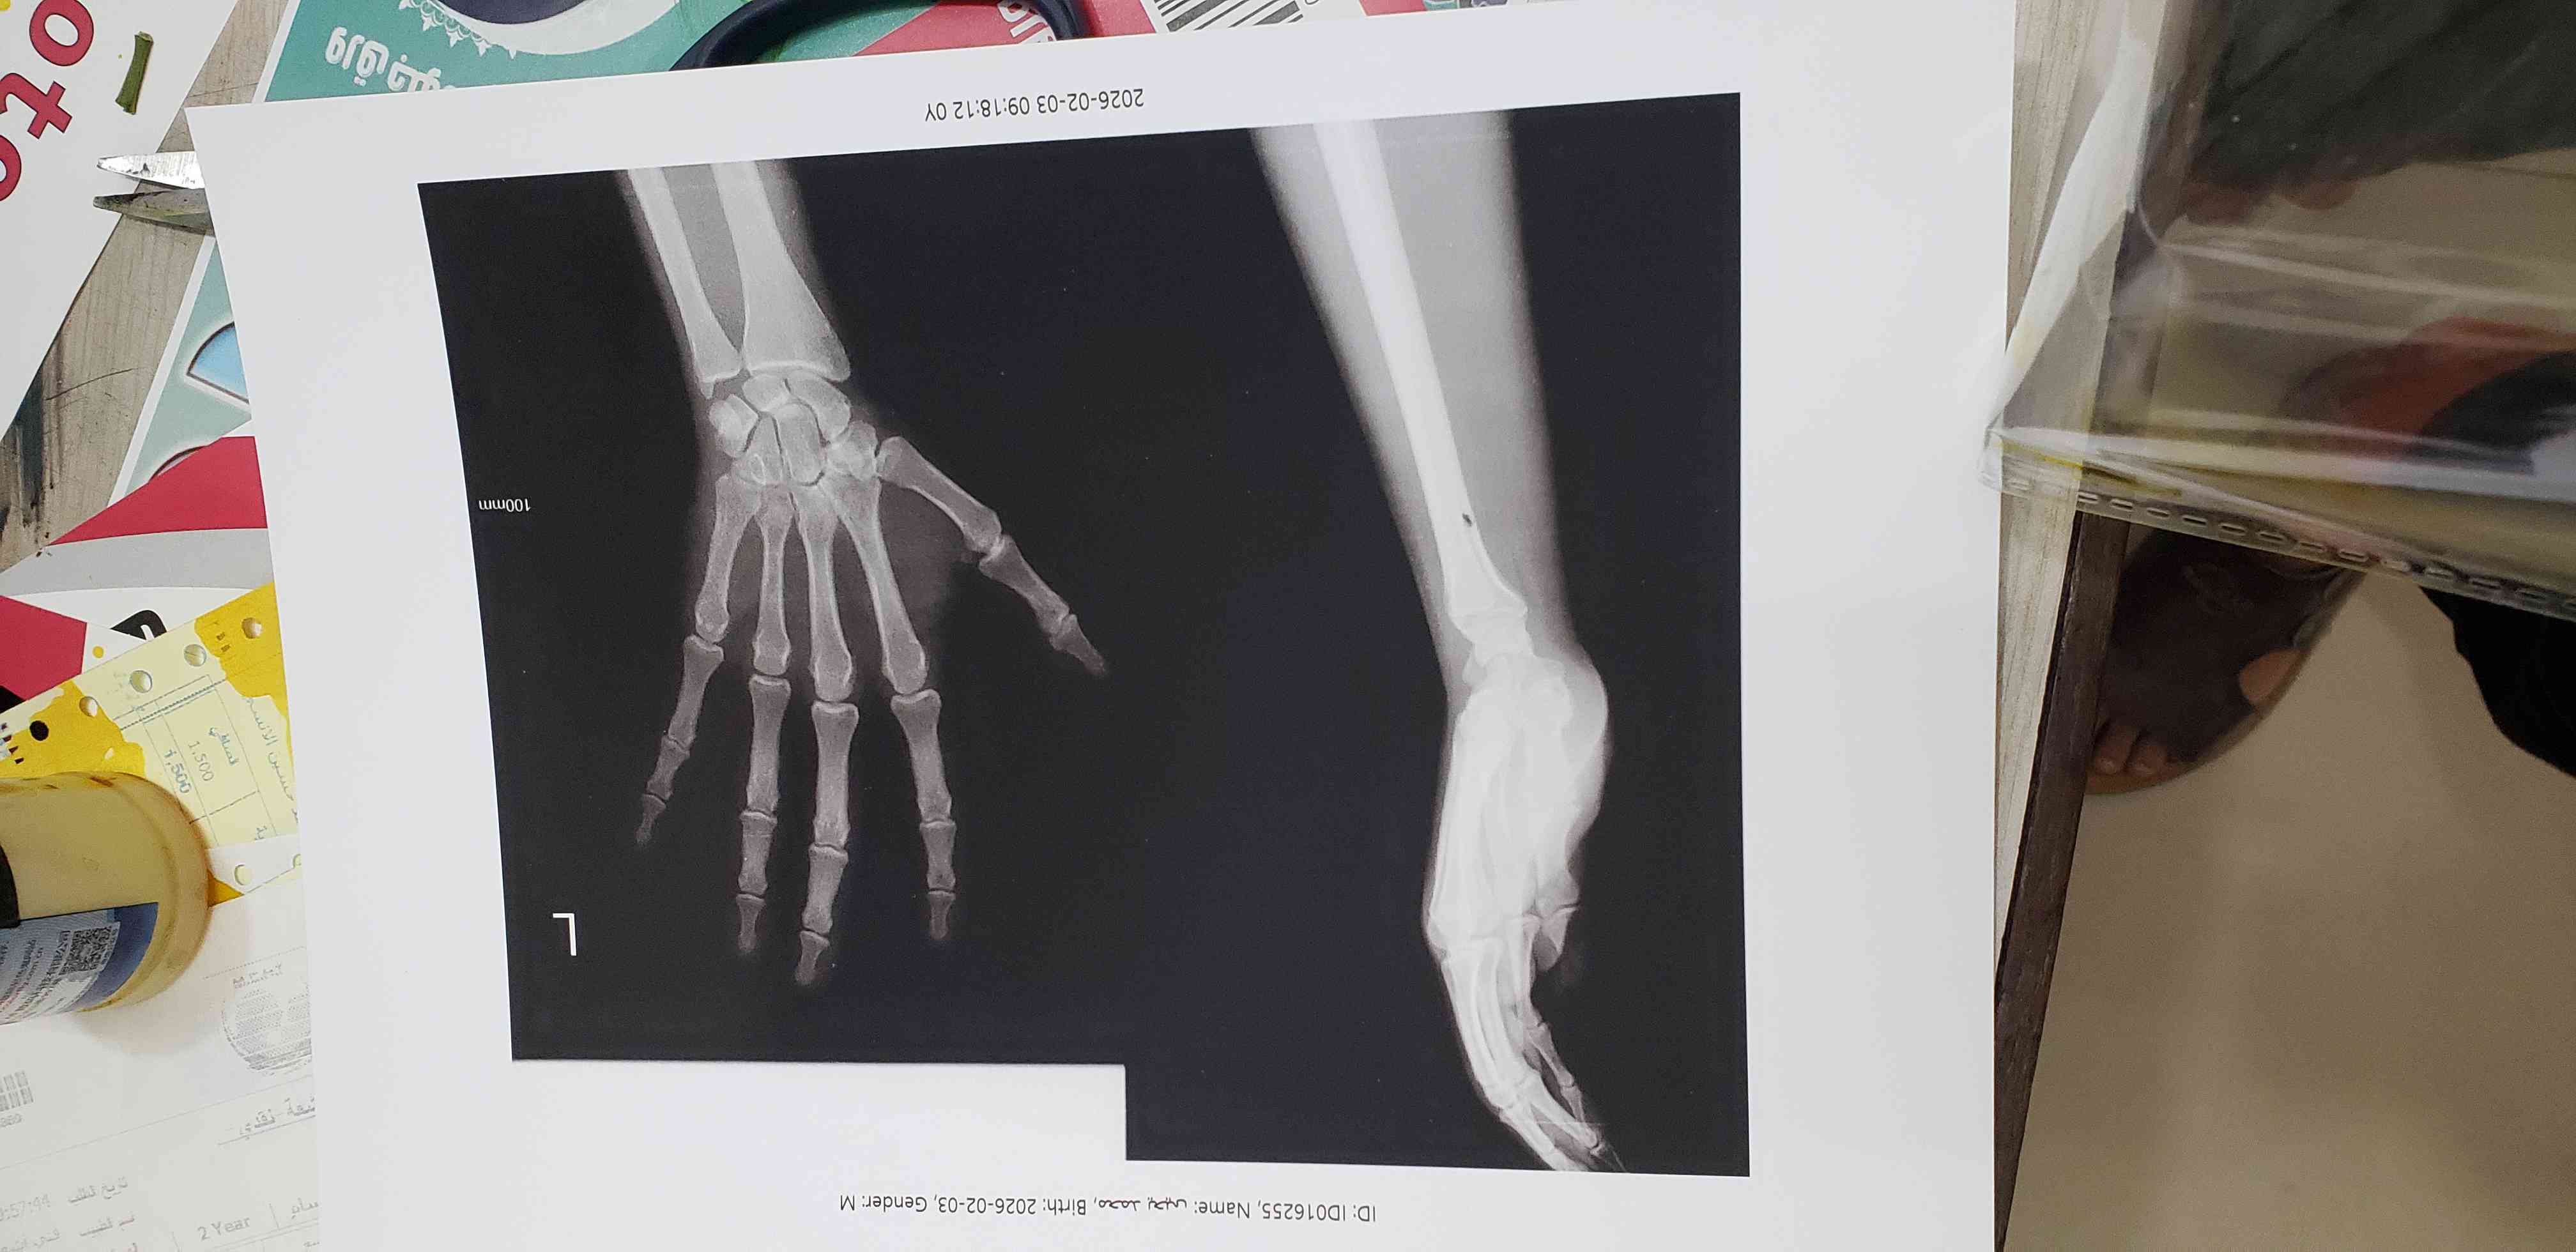

هل صفائح النمو اغلقت ام لا

هل صفائح النمو اغلقت ام لا هل في امل اطول او لا